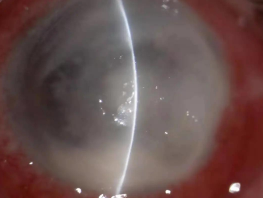

真菌性角膜炎是一種由致病真菌引起的、致盲率極高的感染性角膜病。常見(jiàn)的致病菌為曲霉菌,其次為鐮刀菌、白色念珠菌、頭芽胞菌及鏈絲菌等。可出現(xiàn)免疫環(huán)、衛(wèi)星灶、偽足、菌絲苔被、前方積膿及內(nèi)皮斑。